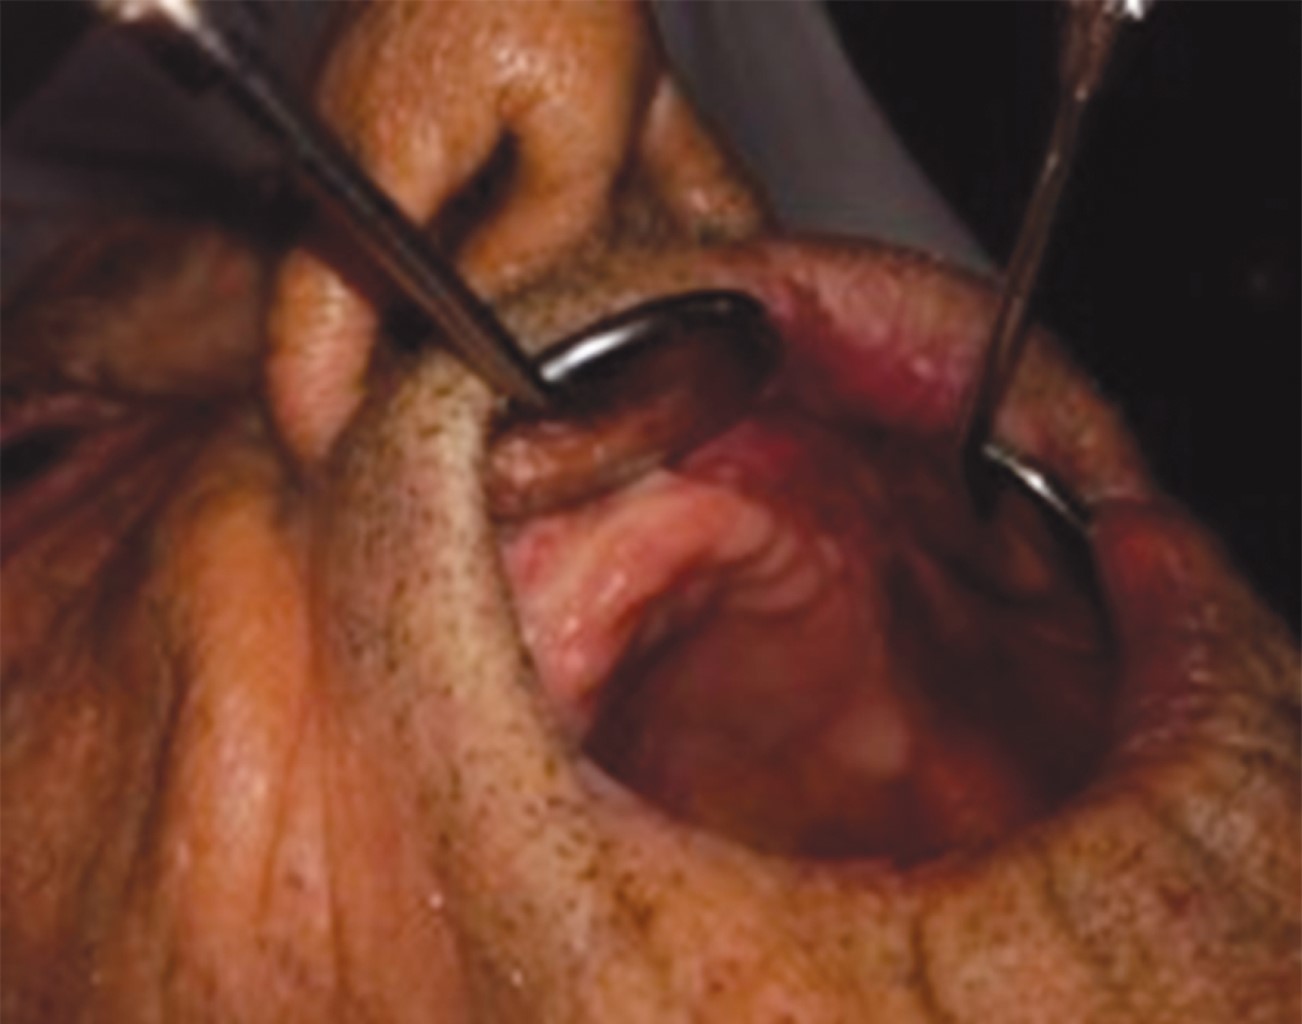

Basal cell carcinoma constitutes 80-90% of all skin cancers and is the most common tumor in humans. It causes a significant impact on the quality of life, with functional and aesthetic morbidity. The anatomical location of the tumor makes us consider reconstructive management, the lips being one of the most complex tumor sites to treat. The reconstruction of large defects of the upper lip constitutes a challenge for the surgeon due to the expectation its results generate not only functional, but also aesthetic. We present the case of a patient with an ulcerated nodular basal cell carcinoma on the upper lip, which was treated by excision and reconstruction with an ipsilateral Gillies fan flap and a contralateral perialar flap with good results.

Figure 2